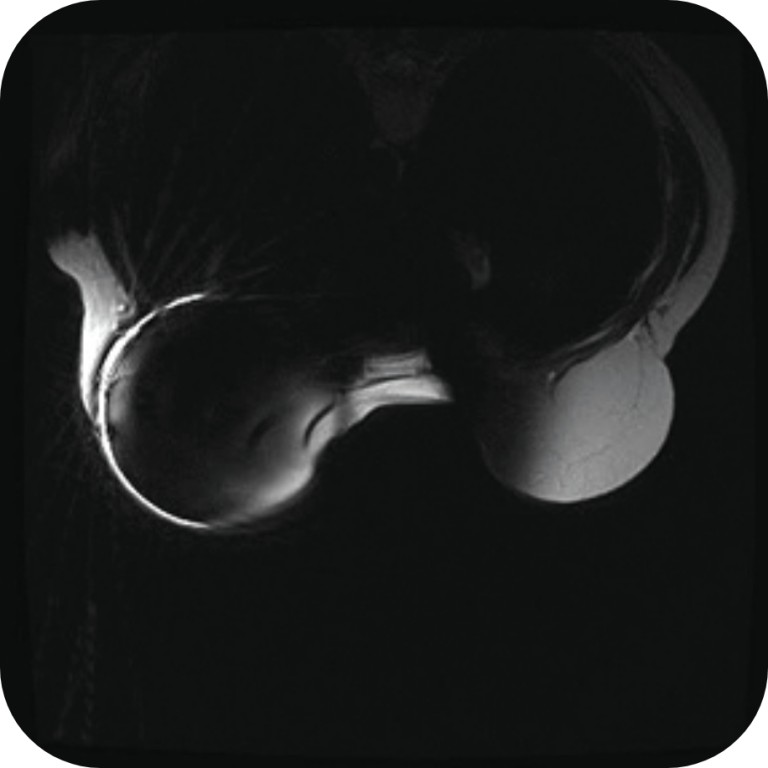

MRI with Traditional Magnetic Port

Traditional magnetic ports create large distortions that impede correct assessment of T1 (a) and T2 (b) in weighted axial MRI images, even in the contralateral breast*.

*Reprinted with authorization: Roller R, Chetlen A, Kasales C. J Am Osteopath Coll Radiol. 2014;3(1):2-9. AOCR